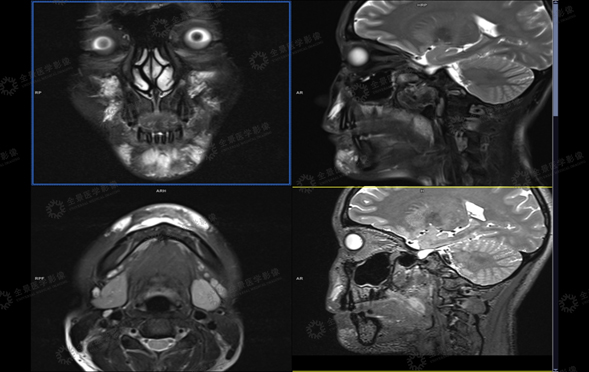

病史:患者女性,26岁,面部玻尿酸填充后,为保证长期的美观性,需了解填充物的分布情况,是否需要再次注射,2020年3月20日来我中心行MRI玻尿酸植入物评估影像检查。双侧额部、面颊部、鼻翼两侧、鼻根部及上颌部皮下见片状异常信号影,T1WI呈稍低信号、T2WI呈高信号。

MR三维重建对于面部填充剂患者能够清晰显示填充剂范围及部位,残留多少及体内形态,可判断填充剂在面部的变化。

填充物-原始分布体积(毫升): |

18.28 |

左侧面部最大厚度(毫米) |

11.4 |

右侧面部最大厚度(毫米) |

10.7 |

下巴部位最大厚度(毫米) |

14.3 |